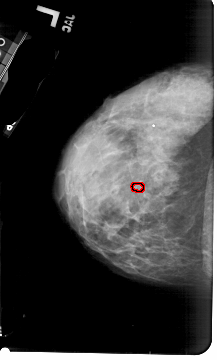

A_1797_1.LEFT_CC

LEFT_CC LINES 5386 PIXELS_PER_LINE 3241 BITS_PER_PIXEL 12 RESOLUTION 43.5 OVERLAY

FILE: A_1797_1.LEFT_MLO.OVERLAY

TOTAL_ABNORMALITIES 1

ABNORMALITY 1

LESION_TYPE CALCIFICATION TYPE PUNCTATE DISTRIBUTION CLUSTERED

ASSESSMENT 4

SUBTLETY 2

PATHOLOGY BENIGN

TOTAL_OUTLINES 1

BOUNDARY